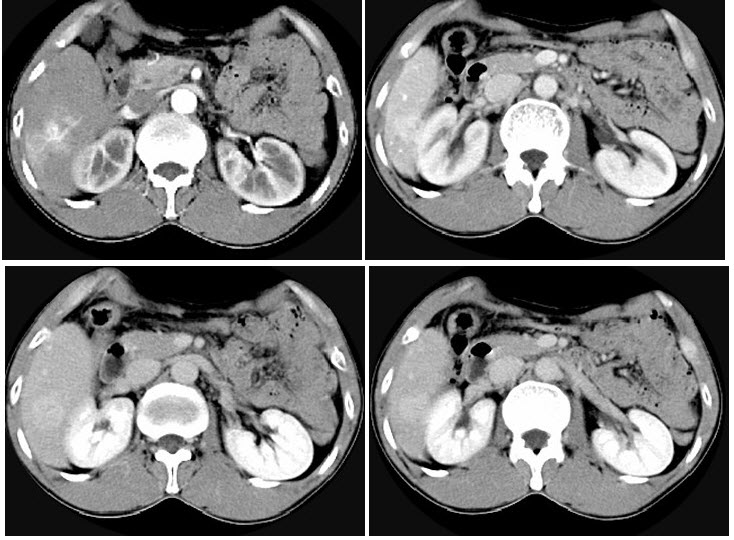

286、多项选择题

1986年Bosniak根据CT征象提出肾囊性病变四级分类法,结合图像,选择正确的说法()

A.右肾内可见一类圆形囊性病灶,边界清楚,增强后无强化

B.该囊性病灶内囊液呈稍高密度

C.此为BosniakⅠ类肾囊肿

D.此为BosniakⅡ类肾囊肿

E.此为BosniakⅢ类肾囊肿